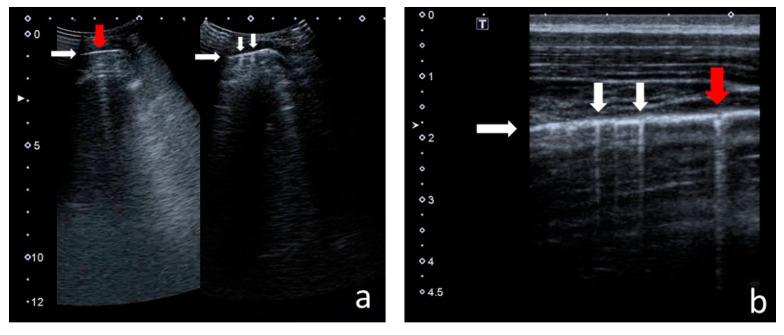

With the increasing longevity of cystic fibrosis (CF), there is a growing need to minimise exposure to ionising radiation in patients who undergo regular imaging tests while monitoring the course of the lung disease. This study aimed to define the role of lung ultrasounds (LUS) in the evaluation of lung disease severity in children with clinically stable CF. LUS was performed on 131 patients aged 5 weeks to 18 years (study group) and in 32 healthy children of an equivalent age range (control group). Additionally, an interobserver study was performed on 38 patients from the study group. In CF patients, the following ultrasound signs were identified: I-lines; Z-lines; single, numerous and confluent B-lines; Am-lines; small and major consolidations; pleural line abnormalities and small amounts of pleural fluid. The obtained results were evaluated against an original ultrasound score. LUS results were correlated with the results of chest X-ray (CXR) [very high], pulmonary function tests (PFTs) [high] and microbiological status [significant]. The interobserver study showed very good agreement between investigators. We conclude that LUS is a useful test in the evaluation of CF lung disease severity compared to routinely used methods. With appropriate standardisation, LUS is highly reproducible.

随着囊性纤维化(CF)患者寿命的延长,在对肺部疾病病程进行监测的同时,尽量减少接受常规影像学检查的患者所受电离辐射的需求日益增加。本研究旨在明确肺部超声(LUS)在评估临床病情稳定的CF患儿肺部疾病严重程度中的作用。对131例年龄在5周至18岁的患者(研究组)以及32例年龄范围相当的健康儿童(对照组)进行了LUS检查。此外,对研究组中的38例患者进行了观察者间研究。在CF患者中,识别出了以下超声征象:I线;Z线;单发、多发及融合的B线;Am线;小实变和大实变;胸膜线异常及少量胸腔积液。将获得的结果与原始超声评分进行对照评估。LUS结果与胸部X线(CXR)结果[高度相关]、肺功能测试(PFTs)结果[相关性高]以及微生物学状态[显著相关]相关。观察者间研究显示研究者之间具有很好的一致性。我们得出结论,与常规使用的方法相比,LUS在评估CF肺部疾病严重程度方面是一种有用的检查方法。通过适当的标准化,LUS具有高度可重复性。